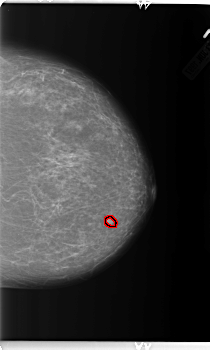

B_3154_1.LEFT_CC

LEFT_CC LINES 5936 PIXELS_PER_LINE 3560 BITS_PER_PIXEL 12 RESOLUTION 50 OVERLAY

FILE: B_3154_1.LEFT_CC.OVERLAY

TOTAL_ABNORMALITIES 1

ABNORMALITY 1

LESION_TYPE MASS SHAPE OVAL MARGINS CIRCUMSCRIBED

ASSESSMENT 3

SUBTLETY 4

PATHOLOGY BENIGN

TOTAL_OUTLINES 1

BOUNDARY